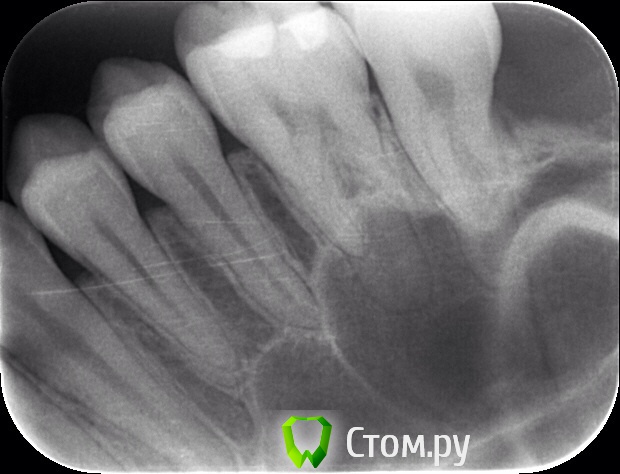

Naga Siren Опубликовано 20 октября, 2014 Автор Поделиться Опубликовано 20 октября, 2014 (изменено) Хорошо, спасибо, я тогда в лс напишу.Прилагаю еще фото Изменено 20 октября, 2014 пользователем Naga Siren Ссылка на комментарий